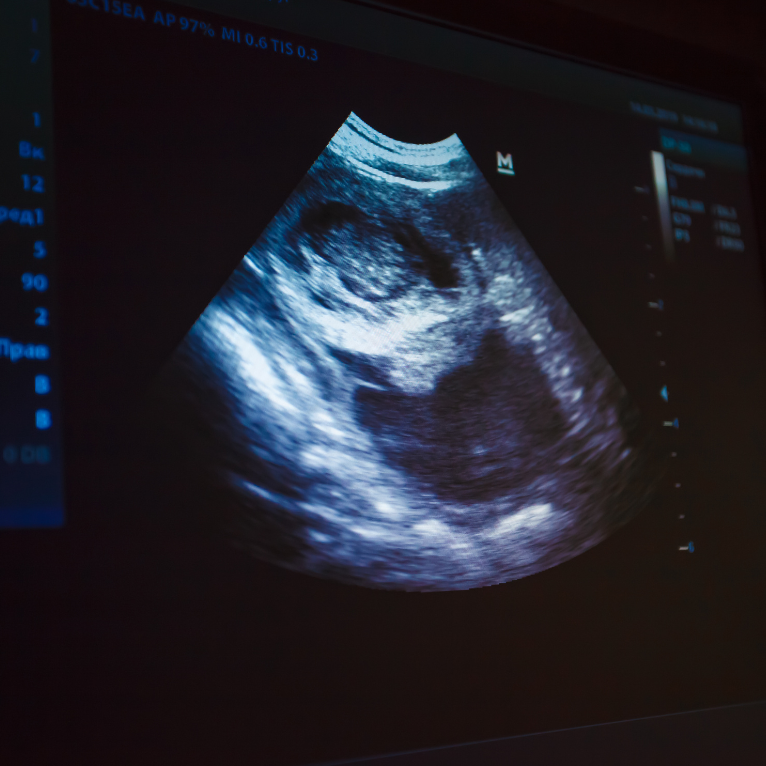

Pregnancy & Childbirth Care

Safe vaginal delivery and Caesarean section (C-section) when medically required, supported by experienced obstetric specialists.